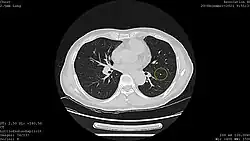

![]() Computed tomography (CT) scanner, a commonly recommended screening technique | |

Results from large randomized studies have recently prompted a large number of professional organizations and governmental agencies in the U.S. to now recommend lung cancer screening in select populations. The 3 main types of lung cancer screening are low-dose, computerized tomographic (LDCT) screening, chest x-rays, and sputum cytology tests.[4] Currently multiple professional organizations, as well as the United States Preventive Services Task Force (USPSTF), the Centers for Medicare and Medicaid Services (CMS) and the European Commission's science advisors[5] concur and endorse low-dose, computerized tomographic screening for individuals at high-risk of lung cancer.

In the following years, the scientific community shifted its attention to computed tomography (CT). In 1996, results were published of a study of 1369 subjects screened in Japan that revealed that 73% of lung cancers that were missed by chest x-ray were detectable by CT scan.[19] Among the earliest United States-based clinical trials was the Early Lung Cancer Action Project (ELCAP), which published its results in 1999.[20] ELCAP screened 1000 volunteers with low-dose CT and chest x-ray. They were able to detect non-calcified nodules in 23% of patients by CT compared with 7% by chest x-ray. While this trial and a similar trial conducted by Mayo Clinic in 2005 demonstrated that CT was able to detect lung cancer at a higher rate than chest x-ray, both these trials used survival improvement, rather than mortality reduction, as an outcome, and thus were unable to prove that the use of CTs in lung cancer screening was actually impacting the number of people dying from lung cancer.[21][18]